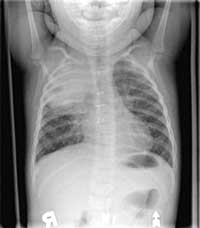

The

CHEST X-RAY is seen below.

Enlarge this CHEST

X-RAY (LEFT). Enlarge this CHEST

X-RAY (RIGHT)

WHAT IS YOUR INTERPRETATION?